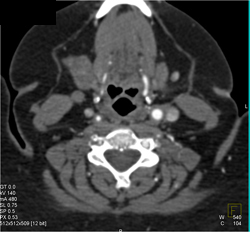

Orbital Fracture Repair